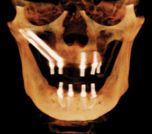

Fig 10 through Fig 12. Representative examples of the use of zygomatic implants for rehabilitation of the severely resorbed maxilla. Fig 10:

Zygomatic implants placed for posterior prostheses support in the absence of sufficient bone in zones 1 and 2 are combined with conventional anterior

implants. Fig 11: Quad zygomatic implants are placed for support of the maxillary prosthesis in the absence of sufficient bone in zones 1, 2, and

3. Fig 12: The unilateral absence of bone in zones 1, 2, and 3 is addressed using unilateral quad zygomatic and conventional implants contralaterally.

Figure 10